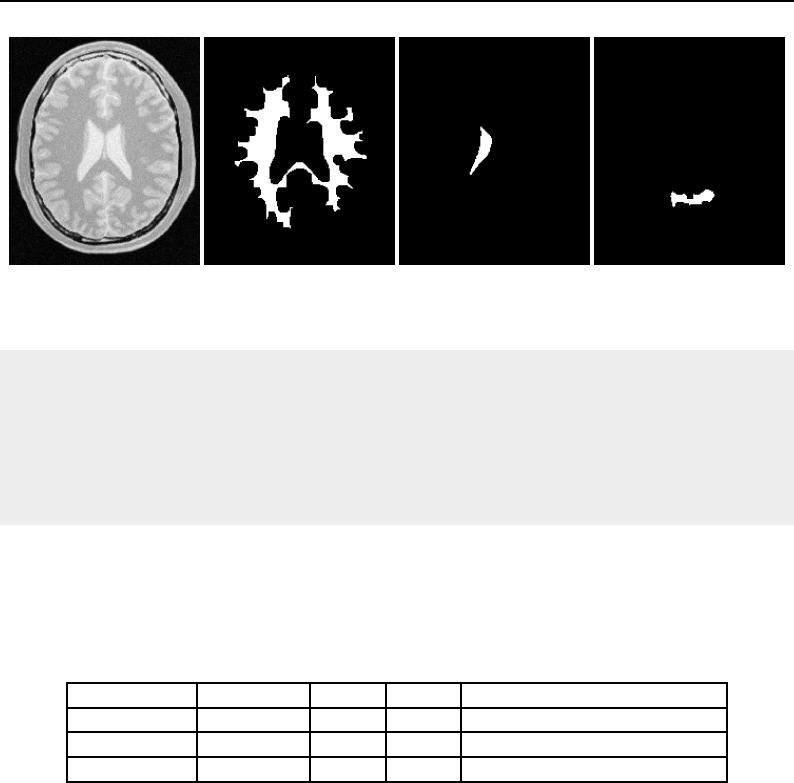

The National Library of Medicine Insight Segmentation and Registration Toolkit, shortened as the

Insight Toolkit (ITK), is an open-source software toolkit for performing registration and segmenta-

tion. Segmentation is the process of identifying and classifying data found in a digitally sampled

representation. Typically the sampled representation is an image acquired from such medical instru-

mentation as CT or MRI scanners. Registration is the task of aligning or developing correspondences

between data. For example, in the medical environment, a CT scan may be aligned with a MRI scan